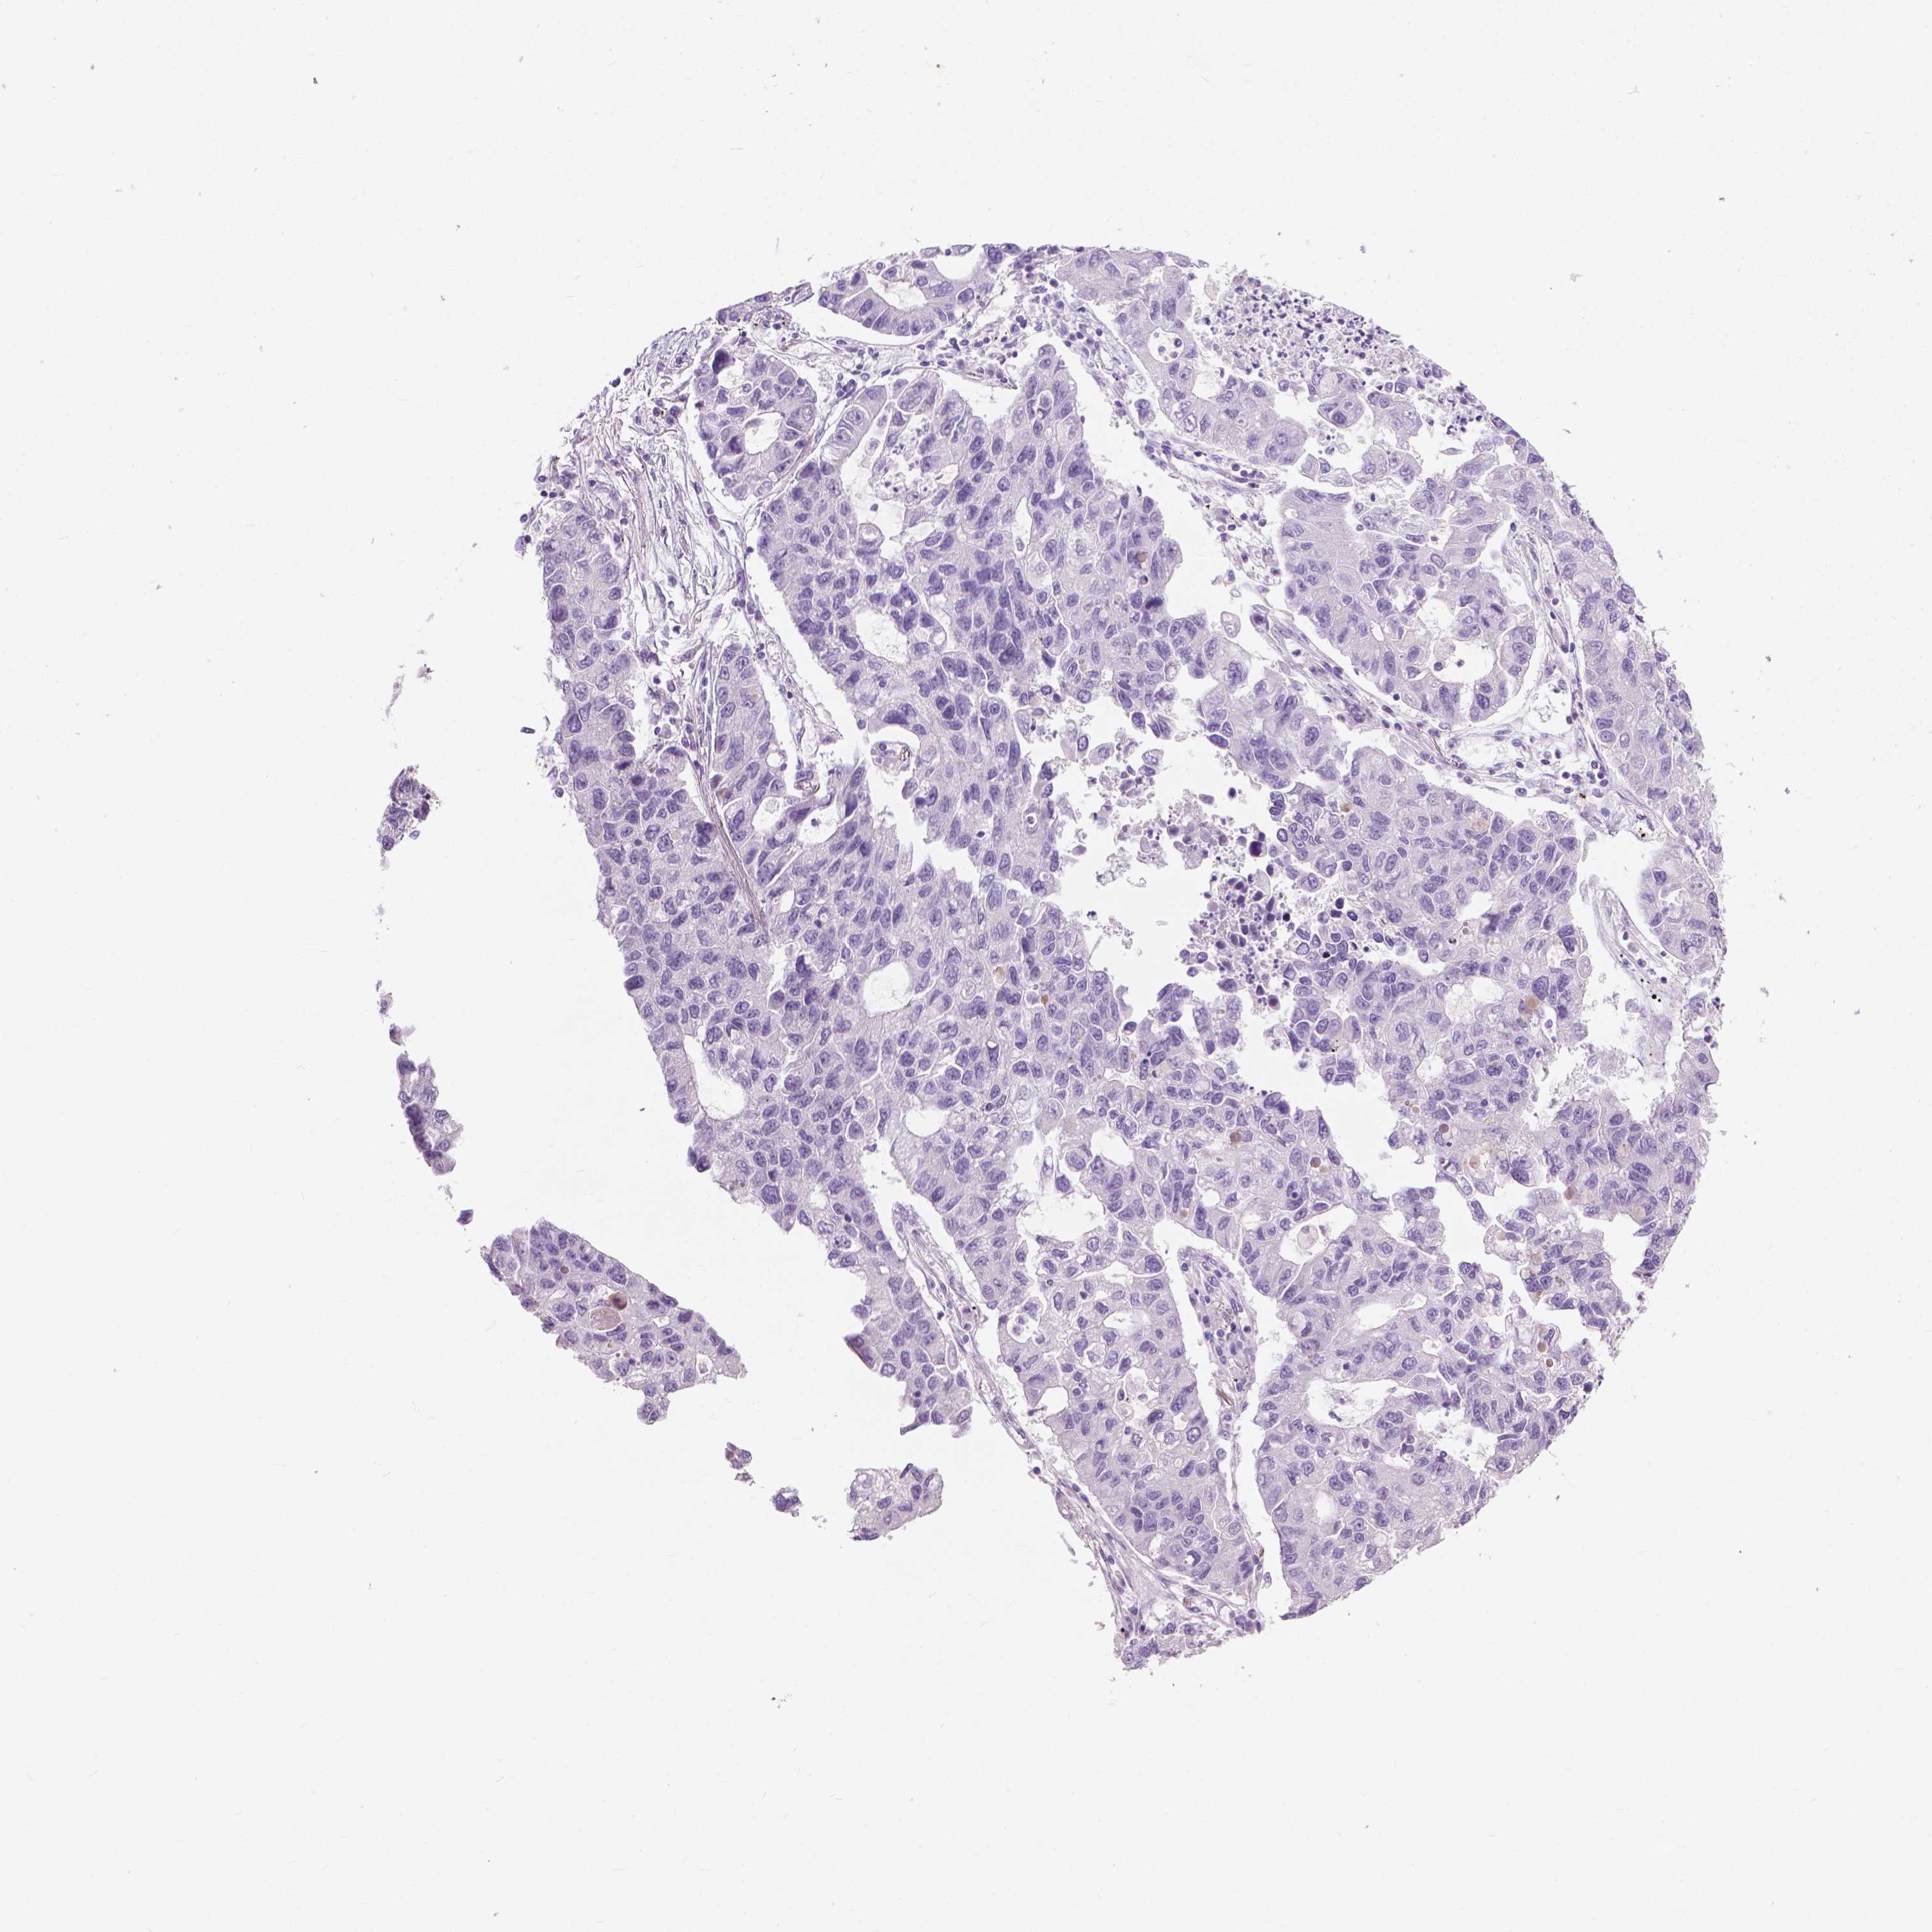

LUNG SQUAMOUS CELL CARCINOMA (TCGA) - Interactive survival scatter ploti

The Survival Scatter plot shows the clinical status (i.e. dead or alive) for all individuals in the patient cohort, based on the same data that underlies the corresponding Kaplan-Meier plots. Patients that are alive at last time for follow-up are shown in blue and patients who have died during the study are shown in red.

The x-axis shows the expression levels (FPKM) of the investigated gene in the tumor tissue at the time of diagnosis. The y-axis shows the follow-up time after diagnosis (years). Both axes are complimented with kernel density curves demonstrating the data density over the axes. The top density plot shows the expression levels (FPKM) distribution among dead (red) and alive patients (blue). The right density plot shows the data density of the survived years of dead patients with high and low expression levels respectively, stratified using the cutoff indicated by the vertical dashed line through the Survival Scatter plot. This cutoff is automatically defined based on the FPKM cutoff that minimizes the p-score. The cutoff can be changed by dragging the vertical line or by entering a cutoff value in the square labeled "Current cut-off".

Under the Survival Scatter plot the p-score landscape (black curve; left axis) is shown together with dead median separation (red curve; right axis). Dead median separation is the difference in median mRNA expression between patients who have died with high and low expression, respectively. It is calculated as follows: median FPKM expression of dead patients with high expression - median FPKM expression of dead patients with low expression. This is intended to aid the user in visually exploring custom cutoffs and the associated p-scores and dead median separation.

Individual patient data is displayed and can be filtered by clicking on one or more of the category buttons on the top of the page. Categories describing expression level and patient information include: high, low, alive, dead, female, male and tumor stages. The scale of the x-axis can be toggled between linear and log-scale by clicking on the "x log" button. Mouse-over function shows TCGA ID, patient information and mRNA expression (FPKM) for each patient.

& Survival analysisi

Kaplan-Meier plots summarize results from analysis of correlation between mRNA expression level and patient survival. Patients were divided based on level of expression into one of the two groups "low" (under cut off) or "high" (over cut off). X-axis shows time for survival (years) and y-axis shows the probability of survival, where 1.0 corresponds to 100 percent.

KRT73 is not prognostic in Lung Squamous Cell Carcinoma (TCGA)

TCGA RNA samplesi

RNA-seq data is reported as average FPKM (number Fragments Per Kilobase of exon per Million reads), generated by the The Cancer Genome Atlas (TCGA) .

Normal distribution across the dataset is visualized with box plots, shown as median and 25th and 75th percentiles. Points are displayed as outliers if they are above or below 1.5 times the interquartile range. FPKM values of the individual samples are presented next to the box plot.

Average pTPM 0.0

Number of samples 489